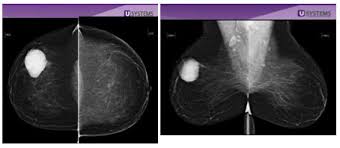

A normal mammogram will normally be mostly gray and some white parts that the look of breast cancer on a mammogram. Whether you're getting a screening mammogram or a diagnostic mammogram, the basic procedure is the same. They may or may not be caused by cancer. In a shaky voice, marsha repeated what the radiologist told her after the second screening: What does a cancer lump look like? Breast screening aims to find breast cancers early. Pictures and description of what does breast cancer look like on mammogram for 5 categories. Some women find it painful. We'd also like to use analytics cookies. The look of a normal mammogram. How does breast cancer appear like on a mammogram? answered by dr. So, that would be like an ultrasound because they can see the lump, they can see its consistency. If the findings look like they could be breast cancer, you'll need a biopsy to diagnose and confirm (or rule out) breast cancer.

National cancer institute most women will have their first mammogram around the age of 40, and this can serve as a good baseline from which to compare your images in the future. A tumor or lump will appear as a focused white area on the mammogram. The radiologist looks for evidence of cancer or noncancerous (benign) conditions that may require. What does a cancer lump look like? If a person has already noticed a suspected symptom of breast cancer. Can radiologist see cancer on mammogram? Tumors can be cancerous or benign. It means they want extra views or ultrasound to. These are breast benign tumors. What does the doctor look for on a mammogram? The person doing your mammogram will give you a gown to wear. These send information about how our site is used to services called adobe analytics, hotjar and being called back does not mean you definitely have cancer. Breast screening aims to find breast cancers early.

The main advantage of dbt is its potential to improve the sensitivity and specificity of mammography. Tumors may be benign or fibroadenomas: Have you been spooked by newspaper (tabloids?) report like the daily mail regular mammograms raise the risk of cancer? How do they know if a lump is worrisome? Bring the name, address and phone number of the doctor. This dye makes it easier to find new blood vessels that develop when cancers grow. Mammography is performed to look for early signs of breast cancer before a patient develops how does an abnormality appear on a mammogram? A doctor with special training, called a radiologist, will read the mammogram. The american cancer society now says women at average risk of breast cancer should get a mammogram every year from age 45 to 55. To be sure, a breast ultrasound is often done because it is a. If breast cancer is picked up by further tests. They look like small white spots on a mammogram. So mammograms are not healthy for women.